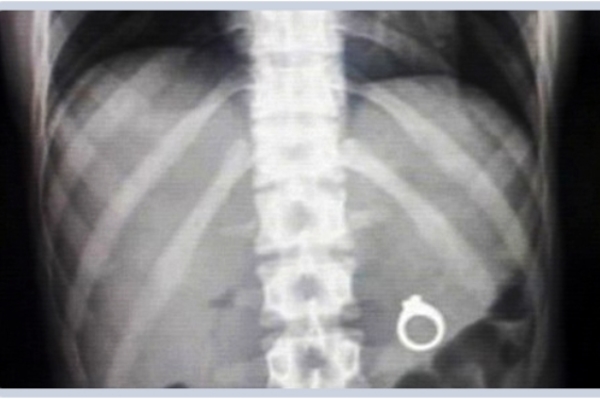

Неожиданные находки в теле человека: ТОП-20 фото

Люди порой поражают медиков странными вкусовыми пристрастиями и удивляют неожиданными вещами, которые по разным причинам оказались в человеческом теле и доступны взору только на рентгеновских снимках. Смотри подборку самых неожиданных находок в человеческом организме

Некоторые люди умудрились удивить медиков странными находками, обнаружившимися в их желудках и телах на рентгеновских снимках. Следует отметить, что многие предметы оказались в человеческом организме волей случая, но некоторые из них - по воле их носителей.